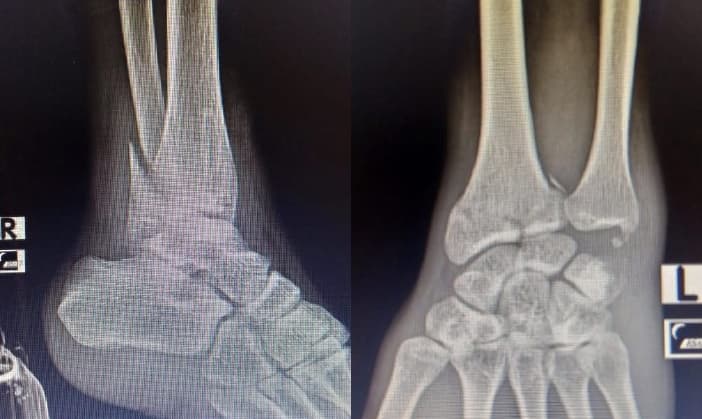

Long story short, saya mengalami kecelakaan motor yang terjadi pada pertengahan 2021 dan mengakibatkan tulang retak di pergelangan kaki kanan dan pergelangan tangan kiri.

Recovery selama 9 bulan lamanya, dimana saat itu saya sulit untuk berjalan dan juga sulit untuk mengetik.